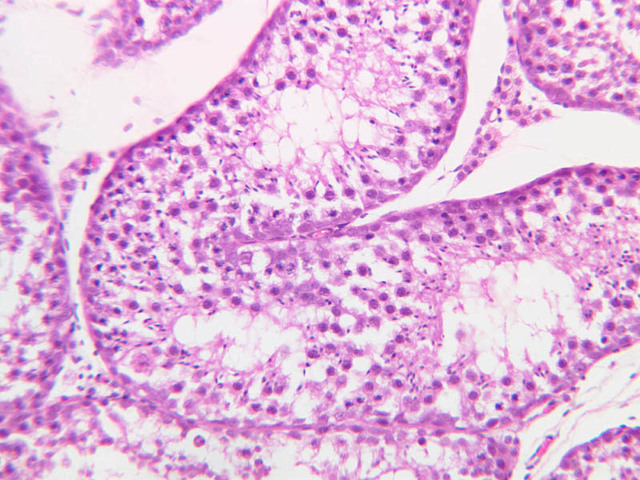

Sperm production, or spermatogenesis, encompasses two distinct series of events: one affecting mostly the nucleus, the other affecting mostly the cytoplasm. First, there is a series of events, known collectively as spermatocytogenesis, in which rounded diploid stem cells (spermatagonia) give rise to clusters of rounded haploid cells (spermatids). Then there is a series of events, known collectively as spermiogenesis, in which the round spermatid spins a long flagellum, undergoes compaction of its nucleus, transforms its Golgi complex into an acrosomal cap, and sheds nearly all of its cytoplasm to yield a spermatazoa. Bear in mind that if you are to develop a good sense of the dynamics of sperm production, you will have to examine a number of seminiferous tubules. This is because spermatogenesis is typified by complex waves of proliferation and differentiation that sweep both around the circumference and along the length of the seminiferous tubule. Using the high dry objective, search slide B-81 for a transversely sectioned seminiferous tubule (i.e. one that presents a round profile in which a large lumen is surrounded by an epithelial wall of uniform thickness). Observe that the peripheral surface is demarcated by a continuous layer of small flattened cells containing elongated basophilic nuclei. These are contractile myoid cells (similar to the myoepithelial cells of other glands), which aid in propulsion of the luminal contents towards the excurrent duct system (B-81, testis, PAS [2.5x-labeled, 10x, 20x. 40x-labeled]; [10x, 20x, 40x]). The clearly stratified seminiferous epithelium differs in appearance from one tubular profile to another and even from one part of a single tubule to another. The seminiferous epithelium is composed of two populations of cells: proliferating cells of the germinal spermatogenic series and nonproliferating Sertoli cells. Sperm production begins with mitotic division of cells located at the tubule periphery; later events occur progressively closer to the lumen. In typical H&E preparations of seminiferous epithelium it is the distinctive qualities of nuclei that stand out against poorly defined cytoplasm (B-80, testis, H&E [20x, 40x-labeled] [10x, 20x, 40x-labeled] [10x, 20x, 40x] [2.5x, 10x, 20x, 40x]; B-82, testis, H&E [2.5x, 10x, 20x, 40x] [2.5x, 10x, 20x, 40x] [10x, 20x, 40x] [10x, 20x, 40x]). Thus, in your study of seminiferous epithelium, it is nuclear appearance that will enable you to distinguish the following cell types:

Primary spermatocytes originate from mitotic division of spermatogonia and are usually one or more cell diameters removed from the tubular periphery. Their nuclei are more or less spherical and are conspicuously larger than those of other germ cells; their chromatin is usually condensed into many thread-like structures. Most primary spermatocytes are seen in some stage of the very protracted (21-day) prophase leading up to the first meiotic (reduction) division, in which each primary spermatocyte gives rise to two secondary spermatocytes.

Spermatids

Spermatids are located next to lumen of the seminiferous tubule, where they undergo an elaborate differentiation process (spermiogenesis) that requires about 7 weeks and involves condensation of nuclear chromatin, compaction and elongation of the nucleus, shedding of nearly all cytoplasm and formation of a motile flagellum (tail). Spermatid nuclei vary in size, condensation of chromatin and shape according to the stage of spermiogenesis that they represent; however, all of them are smaller than the nuclei of any of the antecedent cell types. Spermatids at different stages of spermiogenesis may be present in a single tubule.

Sertoli cells

Interspersed among the germ cells, but generally situated near the epithelial periphery, are nuclei of the Sertoli cells. Sertoli cells span the full thickness of the seminiferous epithelium; however, because of their irregular shape and poor affinity for dyes, it is impossible to define the cytoplasmic processes of Sertoli cells in ordinary paraffin sections. Sertoli cells have large euchromatic nuclei and very prominent nucleoli. The nuclear shape is usually oval or triangular, but may also be irregular due to deep indentations of the nuclear membrane. The long axis of the nucleus is typically oriented at right angles to the basement membrane. From ultrastructural studies it is known that Sertoli cell processes make specialized contacts with germ cells as well as with processes of other Sertoli cells. Sertoli cells are the basis of the blood-testis barrier As you might expect, there are marked differences between the prepubertal and postpubertal testis. In the true prepubertal male (slide B-86, epididymis and testis, H&E [2.5x, 10x, 20x, 40x]) and in undescended testes of older males, the seminiferous tubules are solid cords of cells, consisting of spermatogonia-like cells known as gonocytes, and cells that resemble the Sertoli cells of the adult testis. Section B-78 is from the testis of an older individual and a lumen is now present (B-78, H&E [2.5x, 10x, 20x, 40x]). Even though the seminiferous epithelium of this autopsy specimen is poorly preserved, you should be able to evaluate its spermatogenic capacity. Can you identify spermatogonia and Sertoli cells? Are spermatids present? Judging from the interstitial morphology, would you expect high peripheral testosterone levels?